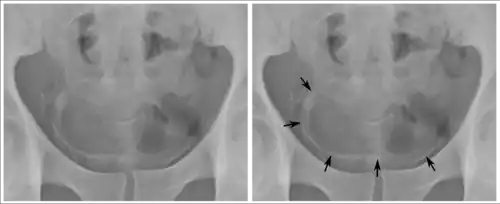

Cancer

Cancer of the bladder is known as bladder cancer. It is usually due to cancer of the urothelium, the cells that line the surface of the bladder. Bladder cancer is more common after the age of 40, and more common in men than women;[33] other risk factors include smoking and exposure to dyes such as aromatic amines and aldehydes.[33] When cancer is present, the most common symptom in an affected person is blood in the urine; a physical medical examination may be otherwise normal, except in late disease.[33] Bladder cancer is most often due to cancer of the cells lining the ureter, called transitional cell carcinoma, although it can more rarely occur as a squamous cell carcinoma if the type of cells lining the urethra have changed due to chronic inflammation, such as due to stones or schistosomiasis.[33]

Investigations performed usually include collecting a sample of urine for an inspection for malignant cells under a microscope, called cytology, as well as medical imaging by a CT urogram or ultrasound.[33] If a concerning lesion is seen, a flexible camera may be inserted into the bladder, called cystoscopy, in order to view the lesion and take a biopsy, and a CT scan will be performed of other body parts (a CT scan of the chest, abdomen and pelvis) to look for additional metastatic lesions.[33]